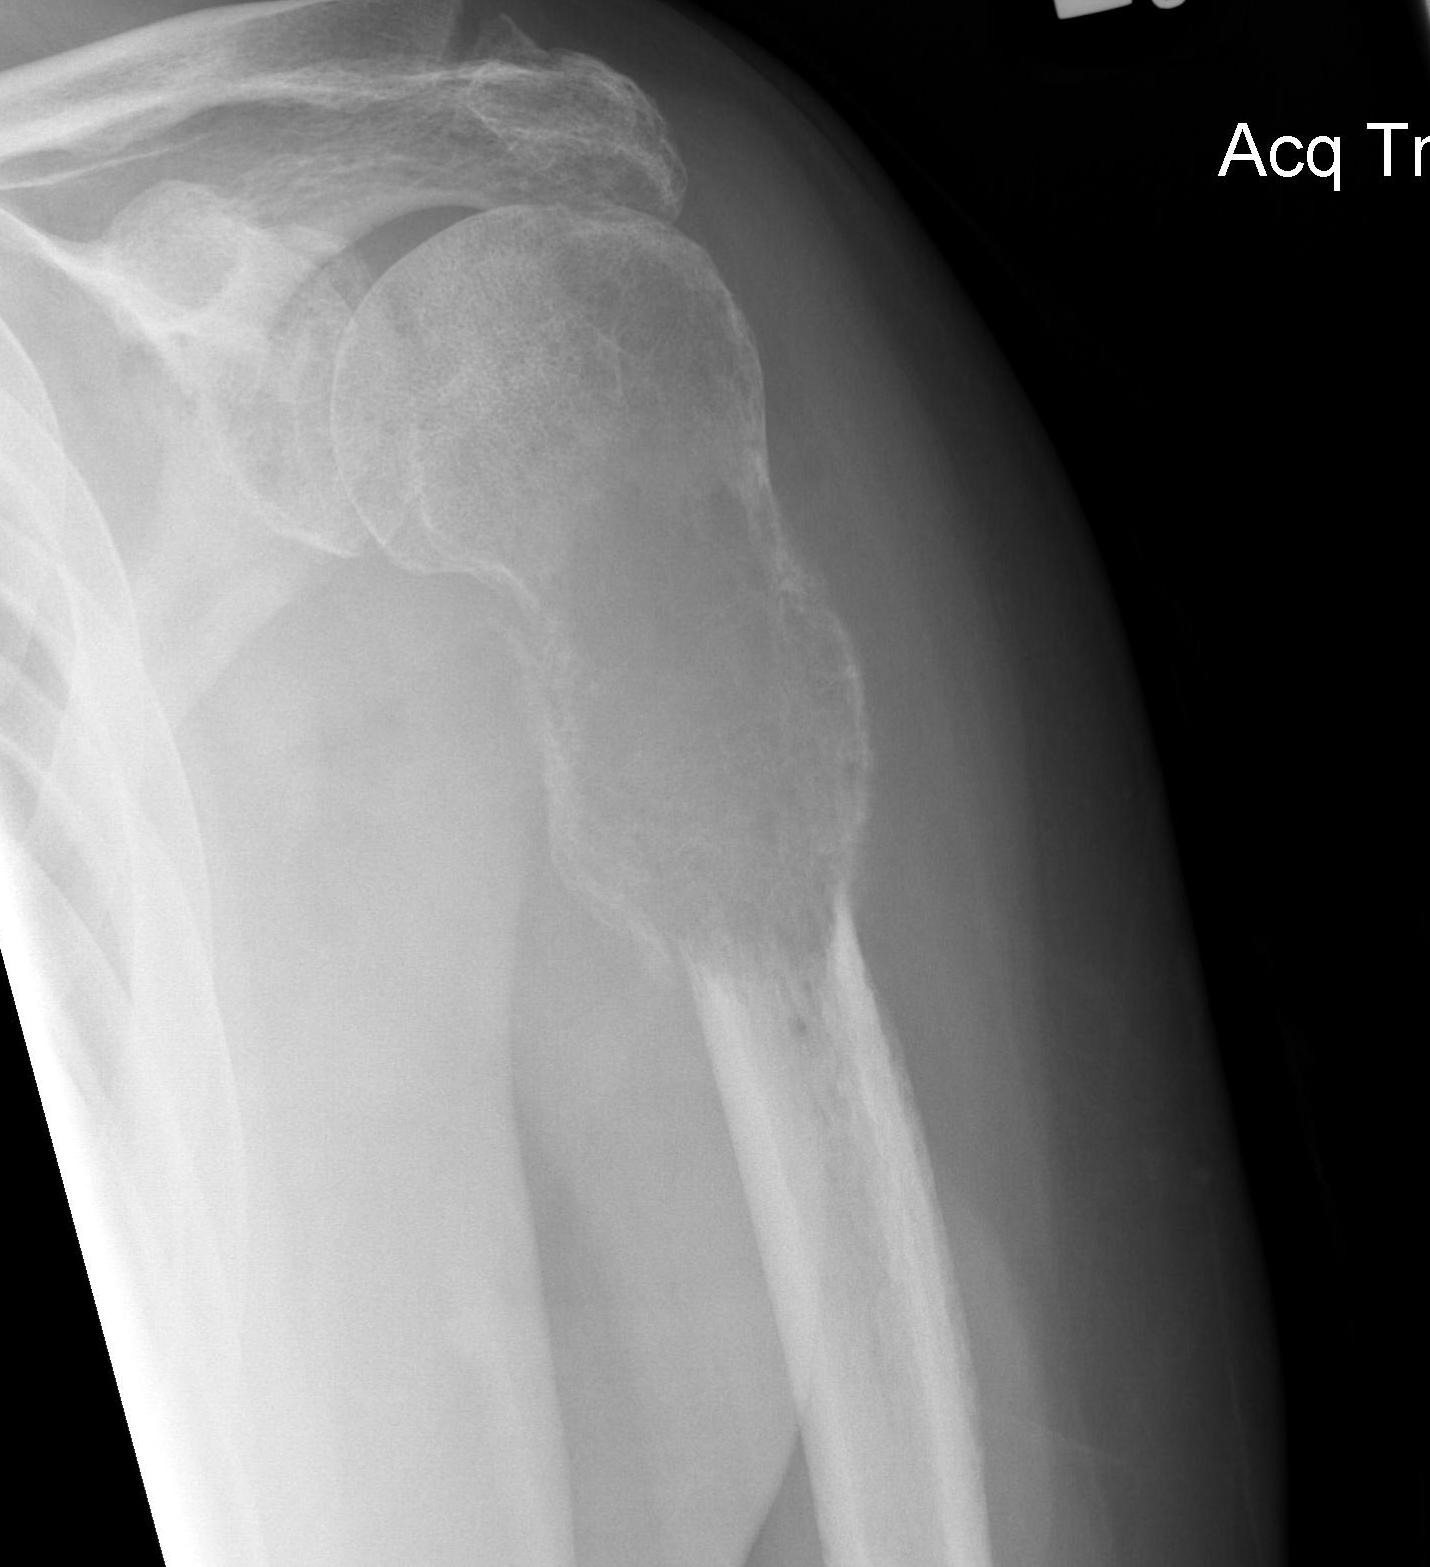

Pre-operative Arterial Embolization

Indications

- renal cell carcinoma

- thyroid carcinoma

Results

- embolisation of RCC metastasis in 107 patients

- success in 96%

- all patients had variable ischemic pain for 2 - 4 day

- 41 cases with embolization prior to surgery compared to 41 cases without

- embolization reduced blood loss, transfusion, and surgical times